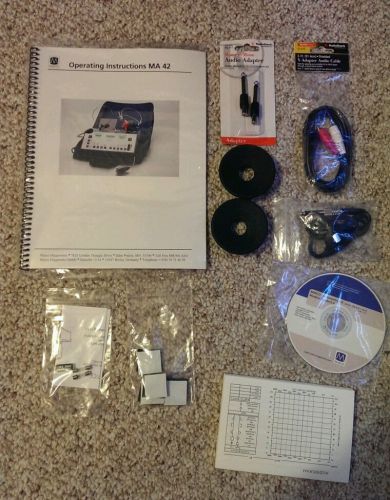

Maico MA 42 Audiometer Operating Instructions with Many Accessories